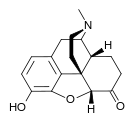

Morphinones and morphols

Structures

| Morphinones and morphols | ||||

|---|---|---|---|---|

14-Cinnamoyloxycodeinone 14-Cinnamoyloxycodeinone |

14-Ethoxymetopon 14-Ethoxymetopon |

14-Methoxymetopon 14-Methoxymetopon |

14-Phenylpropoxymetopon 14-Phenylpropoxymetopon |

7-Spiroindanyloxymorphone 7-Spiroindanyloxymorphone |

8,14-Dihydroxydihydromorphinone 8,14-Dihydroxydihydromorphinone |

Acetylcodone Acetylcodone |

Acetylmorphone Acetylmorphone |

α-hydrocodol α-hydrocodol(Dihydrocodeine) |

Bromoisopropropyldihydromorphinone Bromoisopropropyldihydromorphinone |

Codeinone Codeinone |

Codorphone Codorphone |

Codol Codol(Codeine Phosphate) |

Codoxime Codoxime |

IBNtxA IBNtxA |

Thebacon Thebacon |

Hydrocodone Hydrocodone |

Hydromorphone Hydromorphone |

Hydroxycodeine Hydroxycodeine |

Metopon Metopon(methyldihydromorphinone) |

Morphenol Morphenol |

Morphinone Morphinone |

Morphol Morphol |

N-Phenethyl-14-ethoxymetopon N-Phenethyl-14-ethoxymetopon |

Oxycodone Oxycodone |

Oxymorphol Oxymorphol |

Oxymorphone Oxymorphone |

Pentamorphone Pentamorphone |

Semorphone Semorphone |